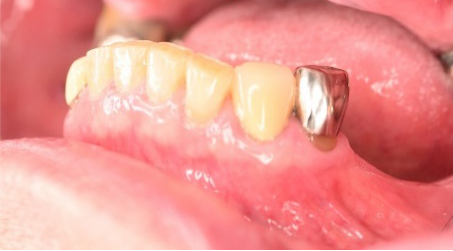

(1)取り外しのバネ式部分入れ歯

(2)歯がないところの両側を削ってつなげるブリッジ

(3)インプラント(それ自身単独で植立し他の歯に負担がかからないし、自分の歯と同じ感覚で噛むことができる)

患者さんは、インプラントを選択されました。インプラントは、他の歯に負担がかからないので、更に歯を失う可能性が低くなりますので、最も良い選択だと考えます。